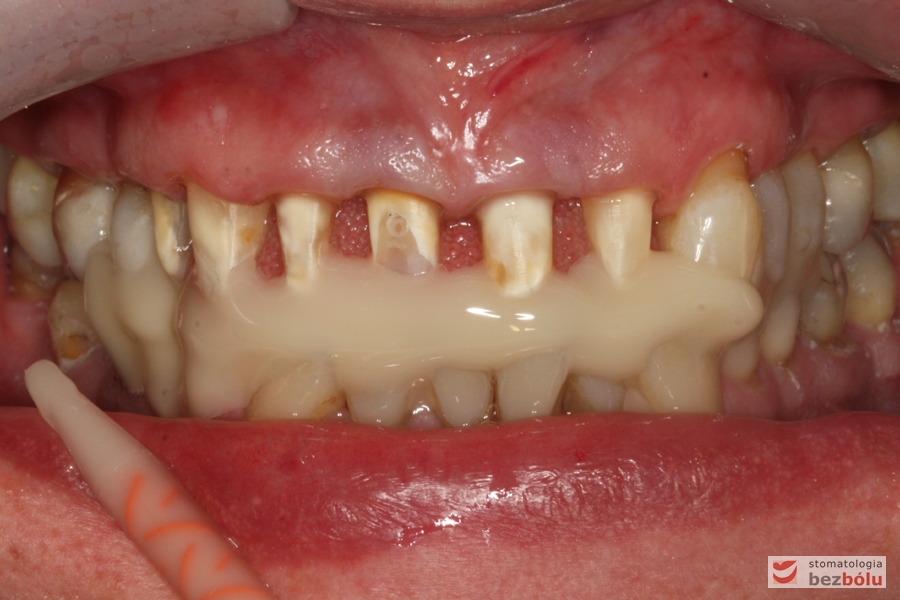

Zęby w zwarciu - widok frontalny, zgryz krzyżowy w pozycji kłów, paradontalny status siekaczy

Zęby w zwarciu – widok frontalny, zgryz krzyżowy w pozycji kłów, paradontalny status siekaczy